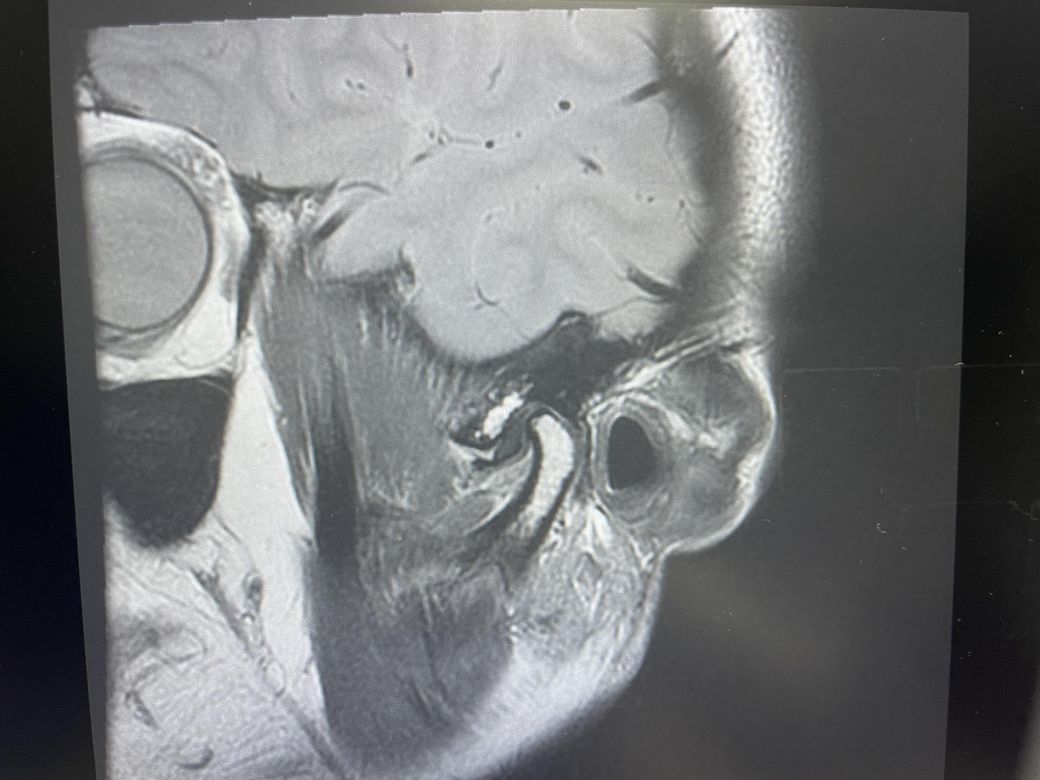

구강내과 턱 MRI 어느 사진이 우측? 좌측?인지 어떻게 보나요? 디스크 두꺼워짐 심한가요?ㅜ

구강내과 턱 MRI 사진 보는데 귀 위치가 다 똑같아서요

어느 사진이 우측? 좌측?인지 어떻게 보나요?

그리고 사진 상 디스크 두꺼워짐 심한가요?ㅜ

현재 사진만으로는 정확히 왼쪽이나 오른쪽이다 라고 할 수 없습니다. 이는 데이터 상의 reference가 필요하며 보통은 해당 부위가 질문자님 기준으로 좌측일 가능성이 가장 크나 이는 좌우 반전을 할 수 있기 때문에 무조건 좌측이라고 할 수 없습니다. 현재 개구시와 폐구시에 보았을 때 condyle (아래턱 부위의 일부)가 disc를 넘어가지 못하고 있으며 이러한 경우 개구제한이 있거나 넘어가더라도 소리가 나면서 넘어갈 수 있습니다. 일부 염증도 보이고 있으므로 내과적인 치료를 하셔야 할 것으로 보입니다.